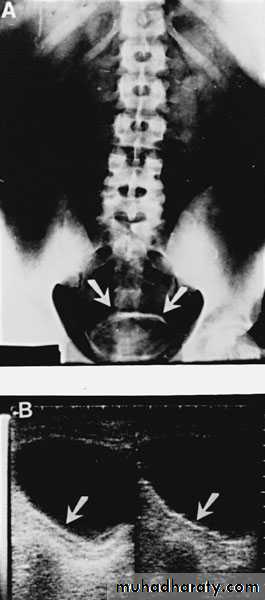

U/S: pus collection around the kidney with or without hydronephrosis.

KUB: obscured psoas shadow, spine scoliosis,.

Drinage of perinephric abscess